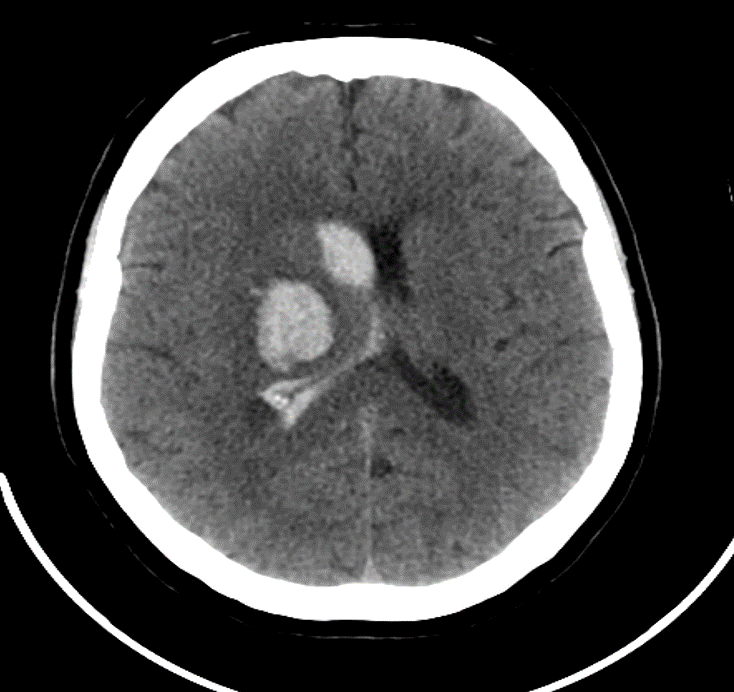

Which imaging modality is usually used as urgent action for a stroke?

Urgent CT scan

What colour does blood show up as on a CT scan of head and neck?

CT is very sensitive for blood – blood shows up as a white on CT – can see this man has a haemorrhage